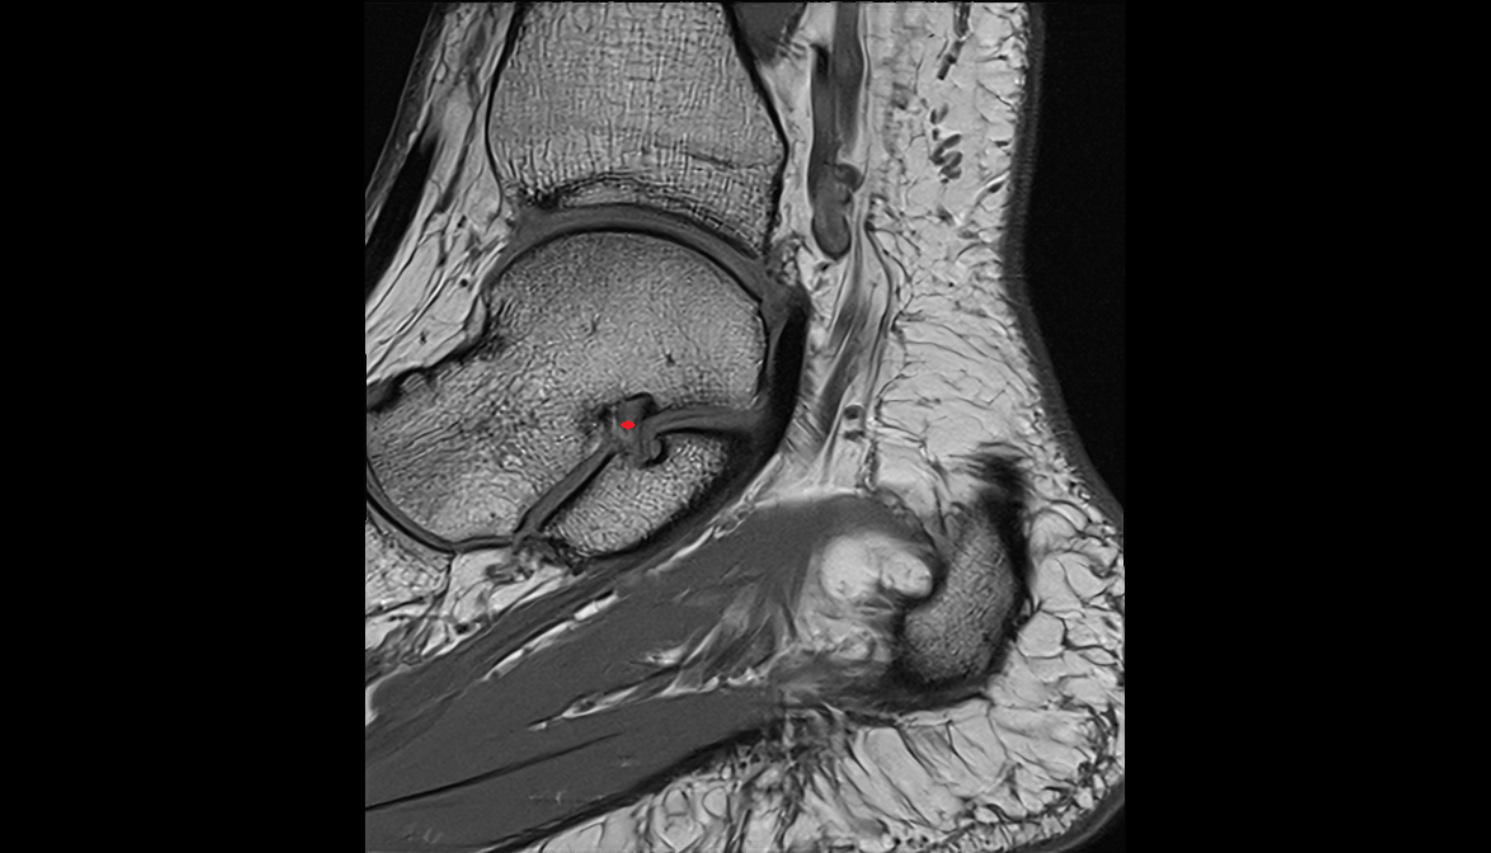

- Talus

- Head of talus

- Body of talus

- Neck of talus

- Calcaneus

- Ankle joint

- Talocalcaneal joint